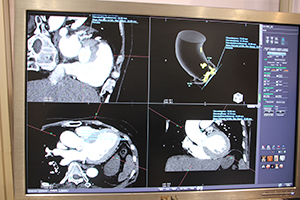

CT心筋ダイナミック血流解析 |

心筋パーフュージョンのデータと冠動脈の情報をマルチデータフュージョンで表示して責任血管などを把握 |